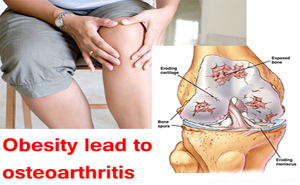

Osteoarthritis is a disease resulting

from wear and tear on joints over time, whereas Rheumatoid arthritis is an

autoimmune disease where the body’s immune system attacks joint tissues. RemoveAvailable Brand

The authors of this study

evaluated the association between weight loss and total knee or hip replacement

for osteoarthritis among middle-aged and older adults with overweight or

obesity. Compared with maintaining a stable weight, weight loss of >7.5% was

associated with a reduced risk of total knee but not total hip replacement.

A weight loss...